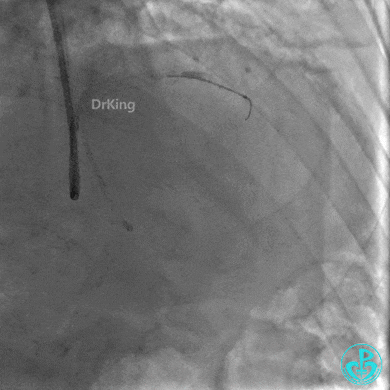

出院后1年复查造影,前降支支架通畅,血流3级。患者无明显胸闷、胸痛、喘憋等症状,日常活动不受限制。